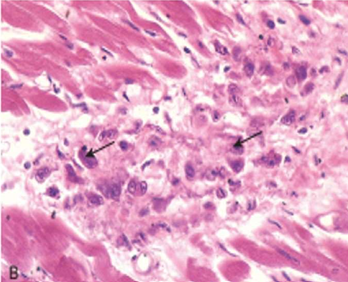

Rheumatic Myocarditis

Aschoff bodies are seen between myocardial bundles as paravascular fusiform collection of mononuclear cells around fibrinoid necrosis